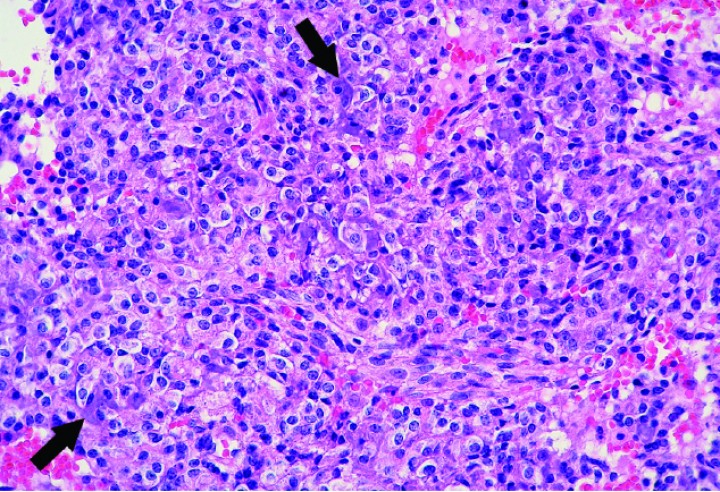

Histológicamente, estos condrosarcomas se caracterizaban por una proliferación de células poliédricas a fibrohistiocíticas o, más raramente, fusiformes dispuestas en nidos, haces o de forma sólida, con depósitos dispersos intercelulares de matriz basófila o anfofílica densa y, en algunos casos, matriz fibrilar eosinofílica que mostraba osificación endocondral o mineralización variable (Figs. 5, 6 y 7); ocasionalmente, se apreciaban zonas con estroma fibroso (Fig. 8).

<p>Cobaya 2. Imagen microscópica de una zona de alta densidad celular de un condrosarcoma caracterizada por células predominantemente histiocíticas dispuestas de forma compacta y que producen muy escasa matriz condroide (flechas). (Hematoxilina y eosina, x400).</p>

Figura 7

Cobaya 2. Imagen microscópica de una zona de alta densidad celular de un condrosarcoma caracterizada por células predominantemente histiocíticas dispuestas de forma compacta y que producen muy escasa matriz condroide (flechas). (Hematoxilina y eosina, x400).